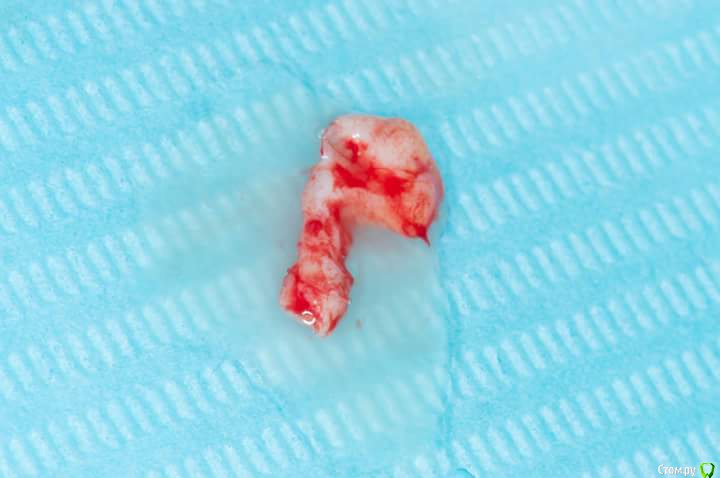

Sampson Опубликовано 3 июля, 2018 Поделиться Опубликовано 3 июля, 2018 1. Забор трансплантата из области 16-17Ушивание2.пластика предверия штрипсой по Урбану3. Установка 2 импланта Adin rpУшивание4.удаление 16. Prf в лунку,поверх губка Альванес. 7 Ссылка на комментарий